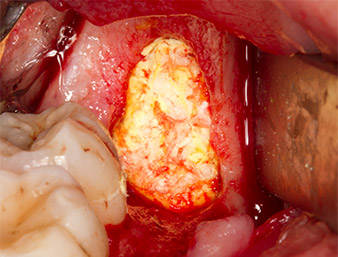

The tissue above the root remnant was not completely ossified and consisted for the most part of granulation tissue modified by inflammation (Fig.4).

To obtain autogenous material for subsequent wound treatment, healthy bone chips were harvested from the surroundings of the root remnant with a piezo surgical instrument (Piezomed B5) (Fig. 5).

Granulation tissue

Fig. 4: Two Langenbeck retractors and a raspatorium expose the operating area. Granulation tissue of the incompletely healed first osteotomy can be seen.

Piezomed B5

Fig. 5: Bone in the region of the alveole is lifted with a chisel-shaped piezo surgical instrument (Piezomed B5). This bone is used as autologous augmentation material after removal of the root remnant (cf. Fig. 13 and 14).

The autogenous tissue was removed with the scraper-shaped section of the working part of the instrument and stored in a physiological saline solution until further use (cf. Fig. 13).

To expose the root remnant with as little trauma as possible to the tissue, a further instrument was used (Piezomed S2) that is primarily indicated for preparing the lateral window in augmentations of the sinus floor. The diamond-coated ball was additionally used to smooth sharp bone edges (Fig. 6 and 7). All the Piezomed attachments were used with the relevant automatic default setting without booster function.